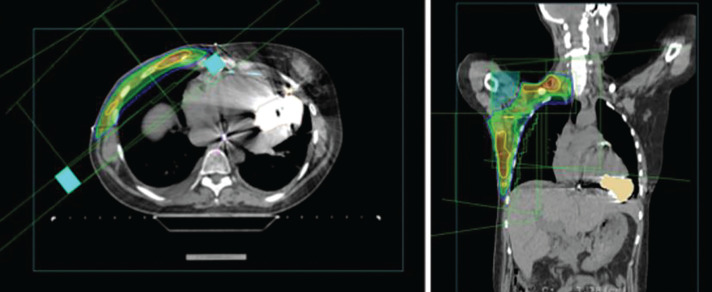

心脏人工装置的使用越来越多,如心脏植入式电子装置(CIED)和左心室辅助装置(LVAD),导致预期寿命更长,因此最终可能与癌症诊断的风险和放射治疗的要求相吻合。cied的安全辐照剂量限值得到了更好的研究和报道,但LVAD辐照的数据很少。我们报告了一例被诊断为乳腺癌的患者,她出现了心力衰竭,并给予了左心室辅助装置,接受了适当的肿瘤治疗,包括化疗、手术,并在仔细的多学科审查后,进行了放疗。患者的右侧初始II期(T1N1)疾病需要对胸壁和局部淋巴结进行放射治疗。进行了细致的放疗计划和治疗交付,并进行了每日LVAD性能检查。在整个治疗期间,LVAD系统接受的最大剂量和平均剂量分别为767 cGy和227 cGy (5000 cGy/25份)。放疗期间及随访41个月,未见VLAD功能障碍。正如这个病例所显示的,有左室辅助装置似乎并不是放射治疗的禁忌症。可能的风险和后果应在多学科背景下进行评估。

The increasing use of cardiac artificial devices, such as cardiac implantable electronic devices (CIED) and left ventricular assist devices (LVAD), results in longer life expectancy and thus may eventually coincide with a risk of cancer diagnosis and requirement for radiotherapy. Safe irradiation dose limits are better studied and reported for CIEDs, but data on LVAD irradiation are scarce. We present a case of a patient diagnosed with breast cancer who developed heart failure and was given an LVAD, received appropriate oncological care including chemotherapy, surgery, and, after careful multidisciplinary review, radiotherapy. The patient's right-sided initial stage II (T1N1) disease necessitated radiation treatment to the chest wall and regional lymphatic nodal areas. Meticulous radiotherapy planning and treatment delivery were performed, and daily LVAD performance checks were done. Maximum and mean doses received by the LVAD system were 767 cGy and 227 cGy, respectively, for the whole treatment period (5000 cGy/25 fractions). During radiotherapy and after 41 months of follow-up, no VLAD malfunction was observed. As this case shows, having an LVAD does not appear to be a contraindication for radiotherapy delivery. Possible risks and consequences should be evaluated in a multidisciplinary setting.